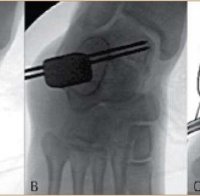

Там през последните години се възстановяват и пациенти с артрозна болест на около 18-20 години, а шиповете им са издайник за дългите часове на компютъра. Липсата на движение довежда до шипове дори в младежка възраст, най-често в колянната става. За ошипяването на лакътя причината може да се търси и в еднообразната позиция с мишка в ръка.

Хроничното натоварване на дадена става също води до шипове, като например при хамалите - на гръбначния стълб, при паркетаджиите - на лактите, при футболистите - на колянна става, пояснява специалистът.